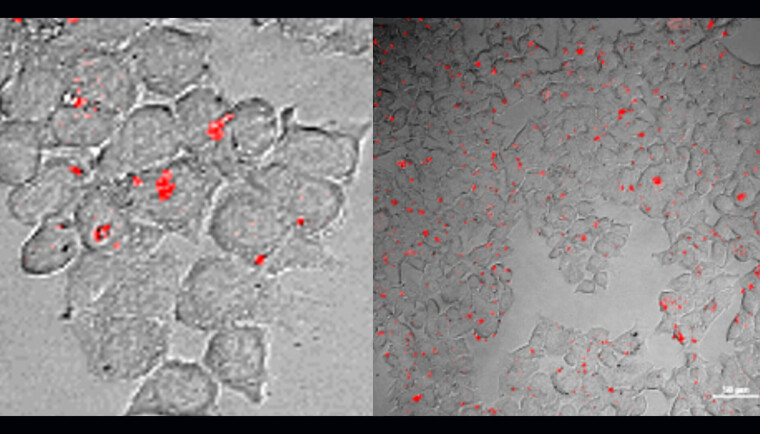

Figure text: The two images show different cell types, HEK 293 and HCT 116, seen through a special microscope. Some of these cells were treated with Tri7C-miR-21/AgNCs (a complex of DNA (Tri7C), microRNA-21 (miR-21) og silvernano-clusters (AgNCs)) for 12 hours, while others were not.

All cells were also treated with lipofectamine, a substance that helps bring molecules into the cells, which attracts microRNA to the kissing DNA structure.

We see red fluorescence from the cells treated with Tri7C-miR-21/AgNCs. In other words, when the cells were treated with Tri7C-miR-21/AgNCs, microRNA-21 lit up in red light, which was captured by the microscope.